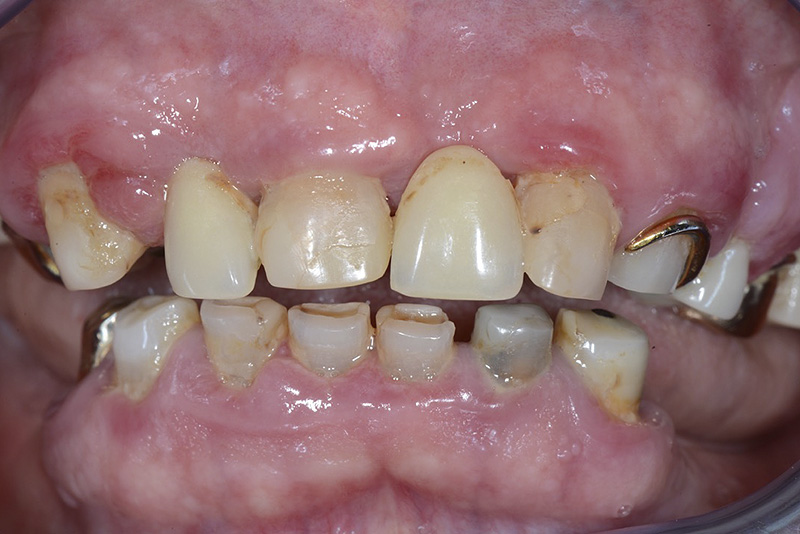

PREMESSA: in seguito all’estrazione dell’incisivo laterale superiore di destra, resasi necessaria per cause batteriche, si decide di affrontare il caso con il posizionamento di un impianto in sostituzione dell’elemento mancante dopo guarigione del sito infetto. Con tecniche rigenerative sia dei tessuti ossei mancanti a causa dell’infezione pregressa, sia dei tessuti gengivali che appaiono inizialmente troppo spostati in alto, si ripristina una corretta morfologia delle parabole (contorni) gengivali e delle papille interdentali (triangoli di gengiva tra due denti vicini).

Vengono utilizzati 2 tipi di provvisori: il primo, cementato ai denti vicini, viene utilizzato dal momento dell’estrazione del dente fino ad impianto osteointegrato (circa 6 mesi); il secondo, avvitato direttamente all’impianto, ha una funzione di prova estetica ma soprattutto di guida per la maturazione dei tessuti gengivali peri-implantari portandoli verso la maturazione completa prima di posizionare la corona finale in disilicato di litio.